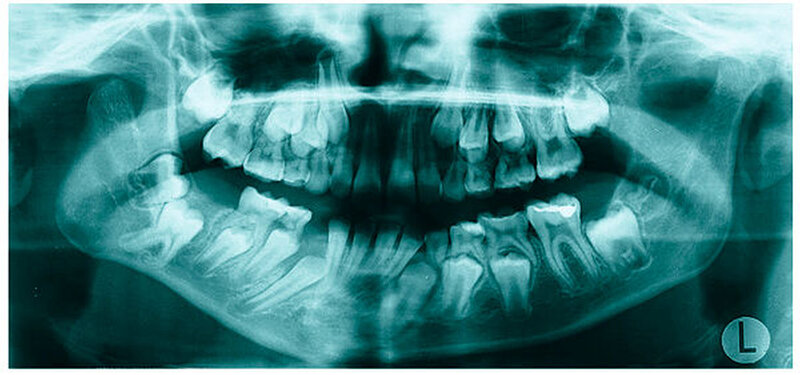

Bereits 2004 wies Carla Evans [Evans, 2005] auf das Risikomanagement bei Allgemeinerkrankungen hin und stellte am Beispiel der JIA dar, dass Unterkieferrücklagen und frontal offene Bisse aus der Kiefergelenkzerstörung entstehen können. Die Röntgenaufnahmen einer JIA-Patientin mit oligoartikulärer Form und Beteiligung des rechten Kiefergelenkes zeigen den typischen Verlauf sehr gut. Bei ursprünglich sehr dezenten Befunden, wie einer s-förmigen Mundöffnung von 44 mm, einer geringen Mittenabweichung um 2 mm nach rechts und einem frontal offenem Biss klagte sie über Schmerzen beim Essen, was den Anlass zur weiteren Diagnostik bot. Die erste Panoramaröntgenschichtaufnahme (Abbildung 1a-c) zeigt auf der rechten Seite einen abgeflachten Kondylus und eine bereits verstrichene Fossa condylaris. Ein Jahr später vermittelt das Fernröntgenseitenbild (Abbildung 1d) trotz fortschreitender kondylärer Resorption ein harmonisches Bild, während nach drei Jahren bei voranschreitendem Abbau des rechten Kondylus (Abbildung 1e) eine Rücklage der Mandibula und eine Bissöffnung manifest sind (Abbildung 1f).

Mithilfe der Panoramaröntgenschichtaufnahme lässt sich in bis zu 67 Prozent der Fälle bereits eine Kiefergelenkdestruktion bei Kindern mit JIA feststellen [Küseler et al., 1998; Twilt et al., 2004; Abramowicz et al., 2014]. Eigene Untersuchungen bestätigten die Eignung als Screening-Verfahren [Mäckelmann, 2008].

Bei 152 durchschnittlich 12-jährigen Rheumapatienten wurden die kondyläre Morphologie und Symmetrie beziehungsweise Asymmetrie im Vergleich zu einer Kontrollgruppe anhand der OPG analysiert. Zur Analyse erfolgte die Zuordnung zu vier morphologischen Graden je Kondylus (Abbildung 3a-d). Bei 45 Prozent der Rheumapatienten waren morphologische Veränderungen im Rahmen kondylärer Resorption unterschiedlicher Ausprägung zu finden. Die „Kontrollpatienten“ ohne JIA zeigten nur zu 14 Prozent formatypische Kondylen. Der Unterschied zwischen den beiden Gruppen war signifikant. Daher sollte bei der Routineauswertung von Panoramaröntgenschichtaufnahmen auf diese Anzeichen geachtet werden, insbesondere auch unter dem Aspekt, dass laut Assaf [2011] durchschnittlich 4,3 Jahre zwischen Erstmanifestation der JIA und Erstvorstellung in der Rheumasprechstunde des UKE liegen.